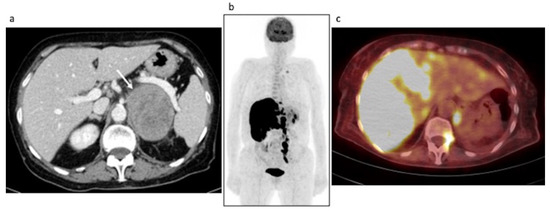

Case #3